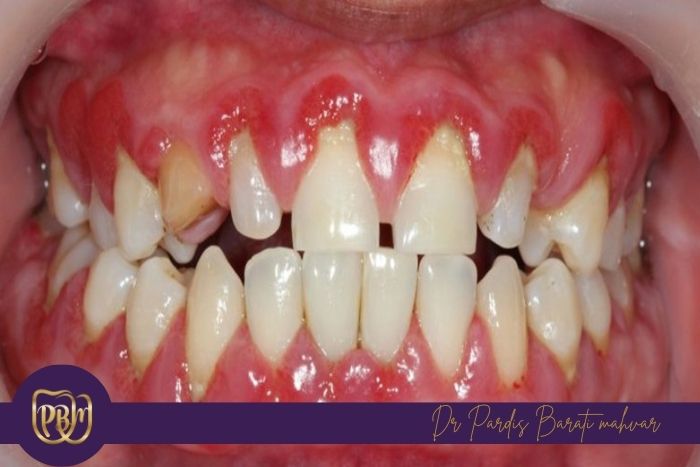

تجمع پلاک و جرم دندانی

زمانی که بزاق به مقدار کافی وجود نداشته باشد، ذرات غذا و باکتریها راحتتر روی سطح دندانها باقی میمانند و شسته نمیشوند.این تجمع سریعتر باعث تشکیل پلاک و سپس تبدیل شدن آن به جرم (تارتار) میشود که میتواند زمینهساز بیماریهای لثه و آسیب بیشتر به دندانها باشد.